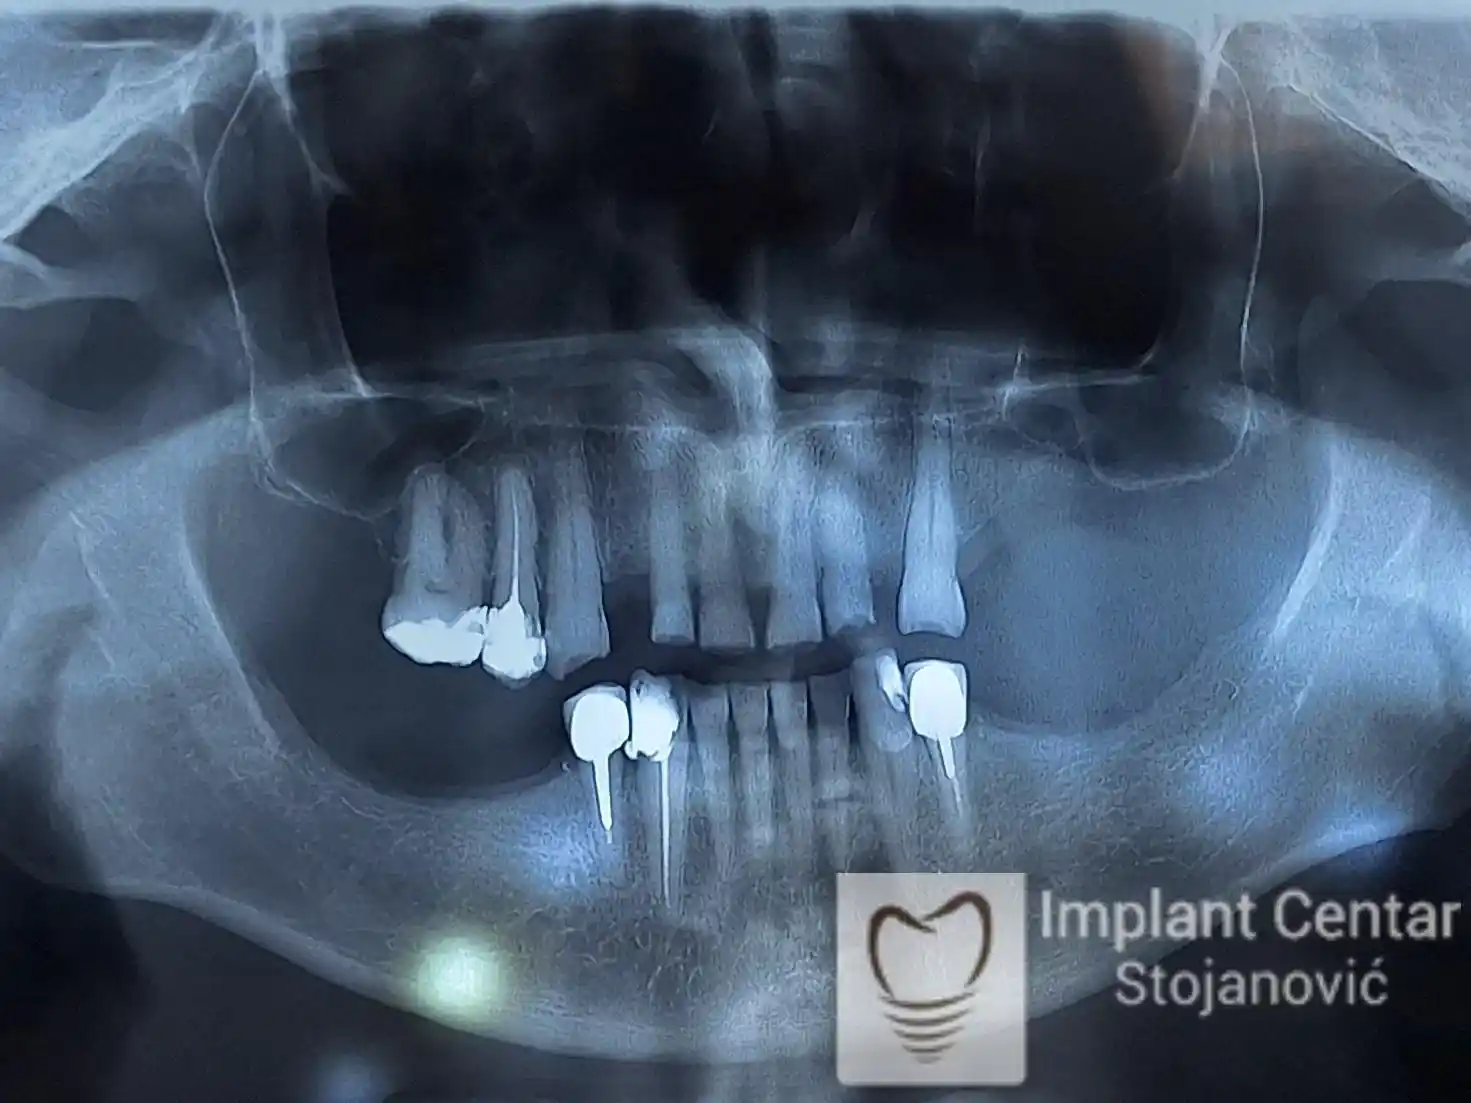

Pacijent sa rascepom usne, nepca i alveolarnog grebena uspešno je rehabilitovan fiksnim protetskim radom na implantatima. Pre dolaska u našu ordinaciju, pacijent je u gornjoj vilici nosio totalnu protezu preko preostalih zuba, dok je u donjoj vilici bio zbrinut parcijalnom mobilnom protezom. Tokom višegodišnje potrage za adekvatnim rešenjem, pacijent nije uspeo da pronađe zadovoljavajuću terapijsku opciju ni u zemlji ni u inostranstvu.

Nakon detaljnog kliničkog pregleda i analize radioloških snimaka, izrađen je sveobuhvatan plan terapije sa ciljem uklanjanja mobilnih proteza i postizanja maksimalne funkcionalne i estetske rehabilitacije. Zbog loše biološke vrednosti preostalih zuba, doneta je odluka o njihovom vađenju i ugradnji dentalnih implantata.

Poseban terapijski izazov predstavljalo je premošćavanje defekta nastalog usled rascepa, kao i ograničena količina raspoložive kosti u gornjoj vilici. Primenom većeg broja implantata i odgovarajućih procedura nadoknade kosti, postignuta je stabilna osnova za fiksni protetski rad.